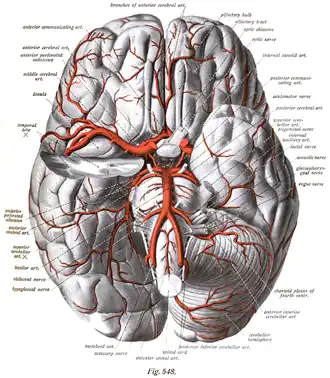

The arteries of the base of the brain. Basilar artery labeled below center. The temporal pole of the cerebrum and the cerebellar hemisphere have been removed on the right side. Inferior aspect (viewed from below). | |